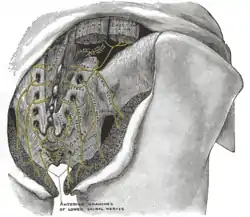

Left levator ani from within. The posterior divisions of the sacral nerves.

The posterior divisions of the sacral nerves. Sacrum. Pelvic surface.